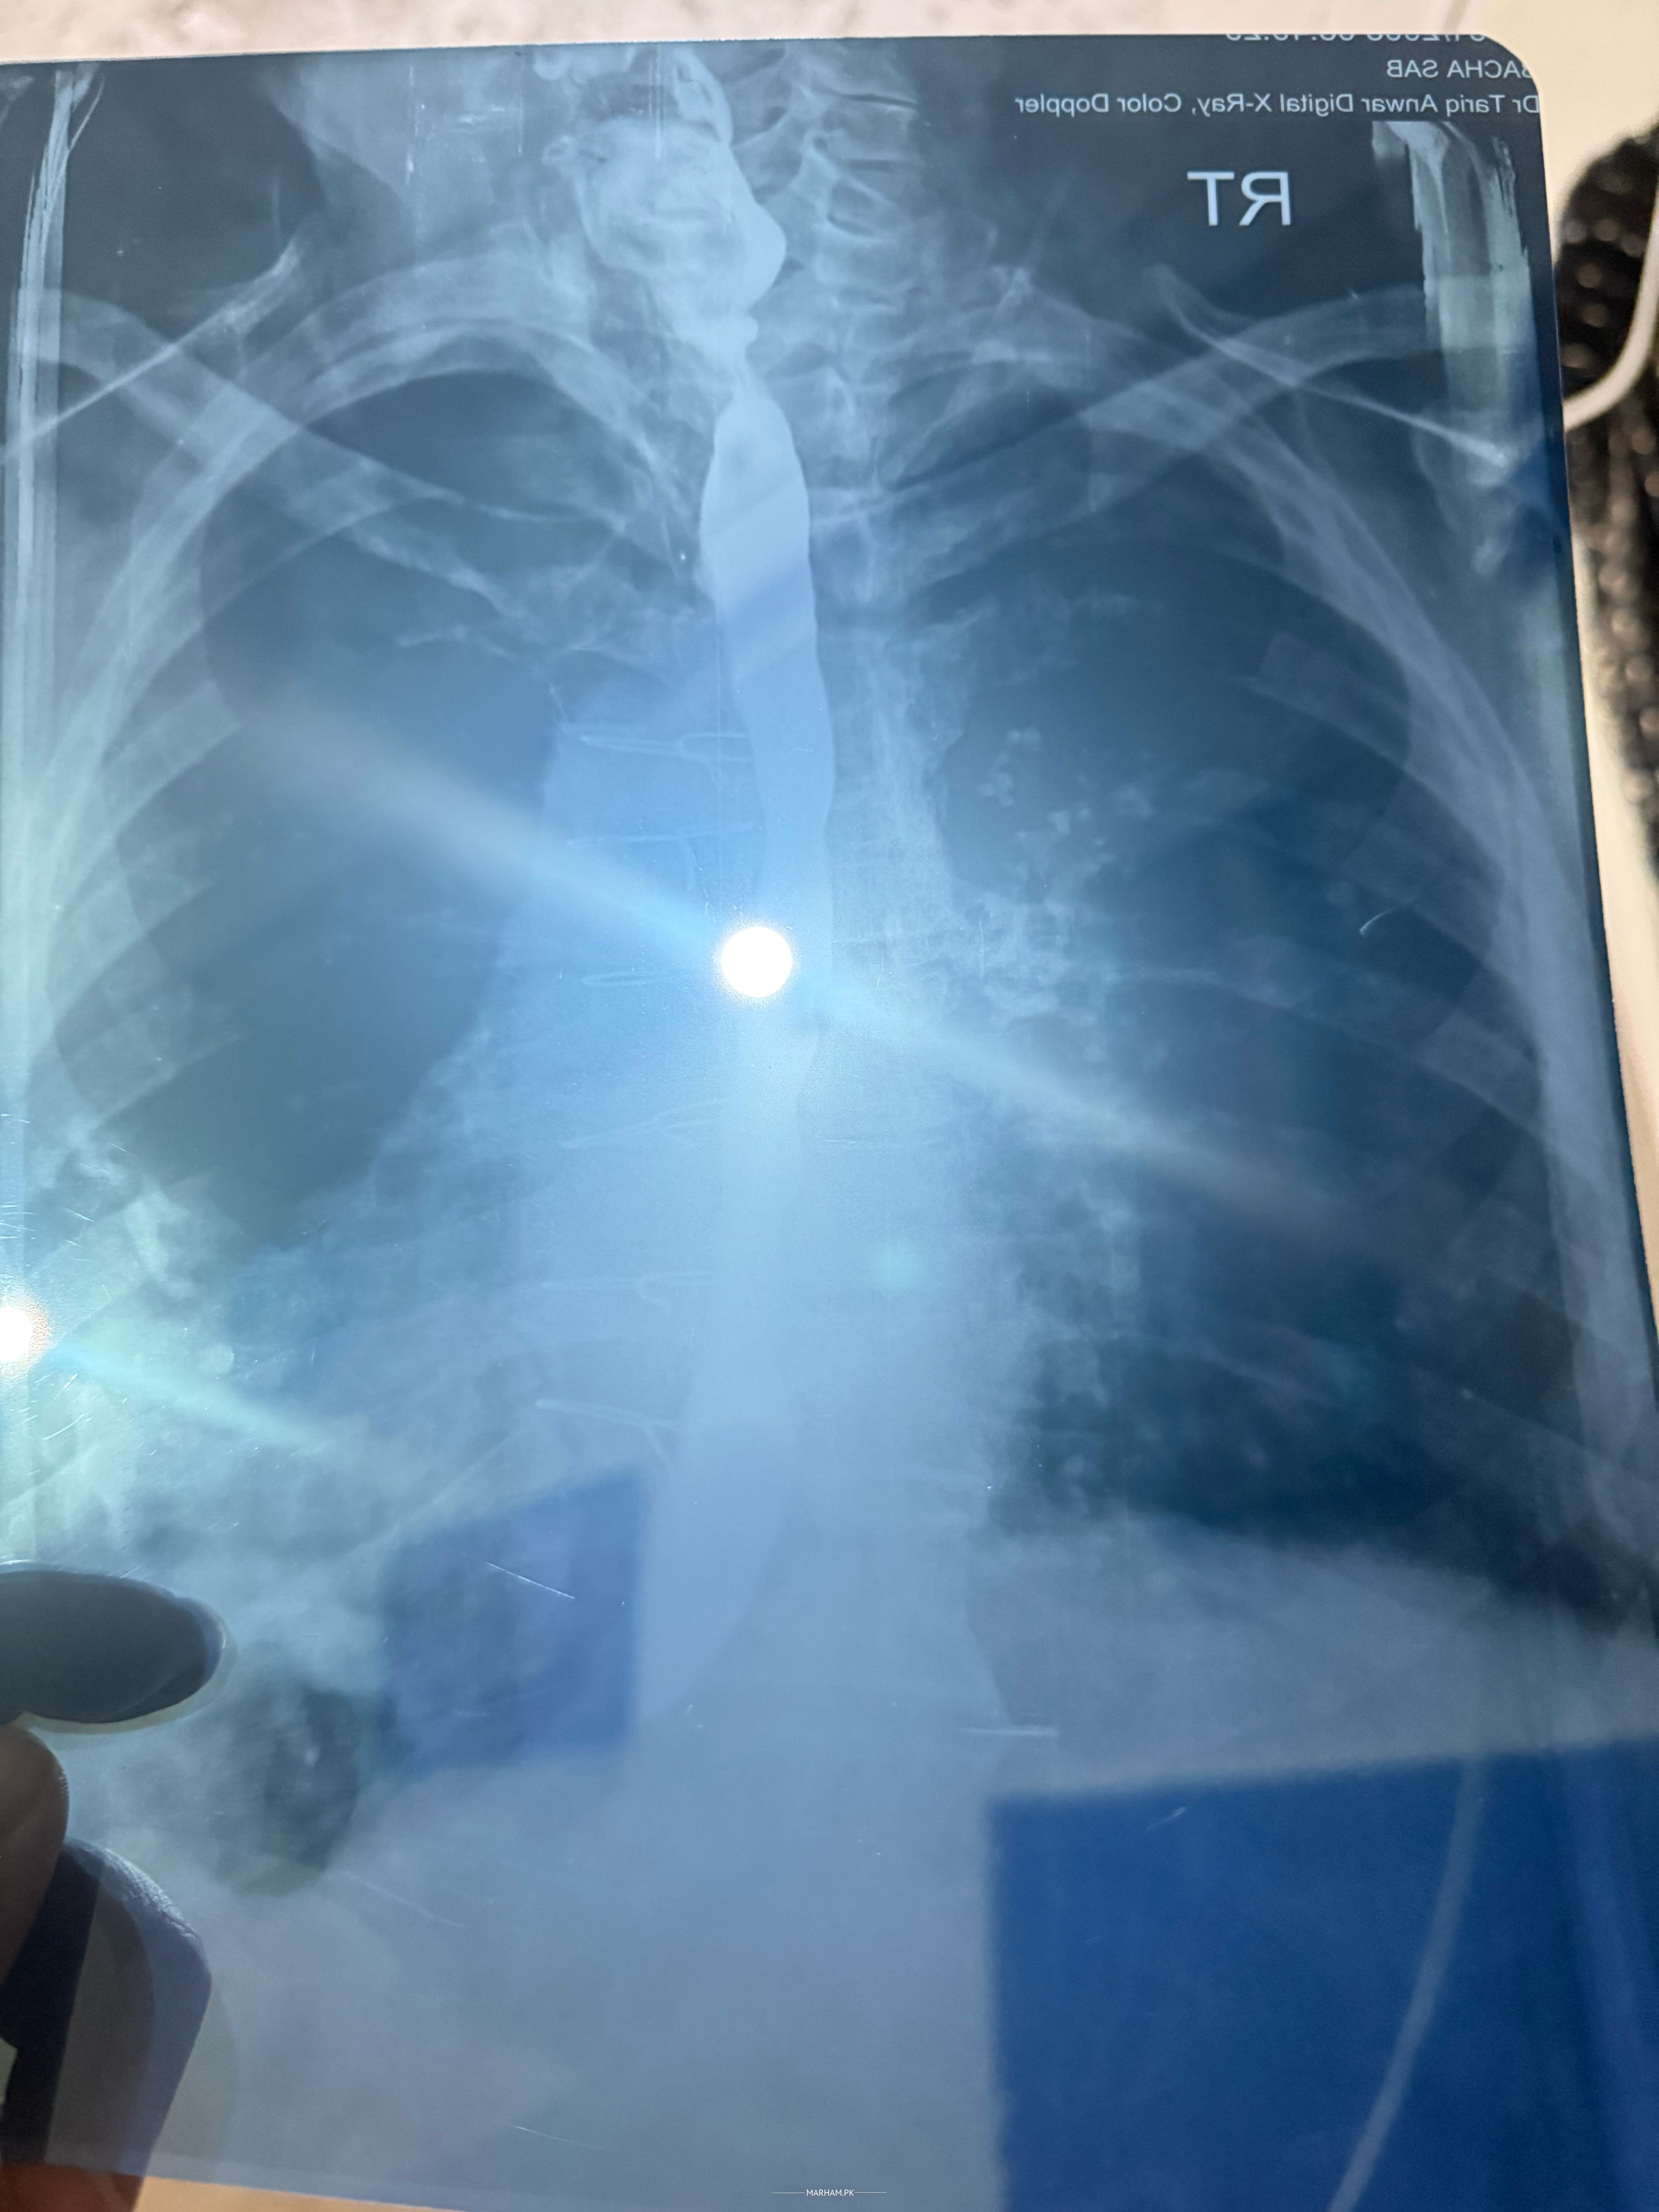

Mere walid sab ki xray report share kiye hai mashwra dijaye causes kya hai aor treament kya hai ? Aor he koi cance toh nhi tumor etc?

unable to fully understand due poor quality of notes. most probably you're father has dysphagia due to esophageal narrowing/Esophageal fistula. please consultant a nearby gastroenterologist for proper diagnosis and treatment.